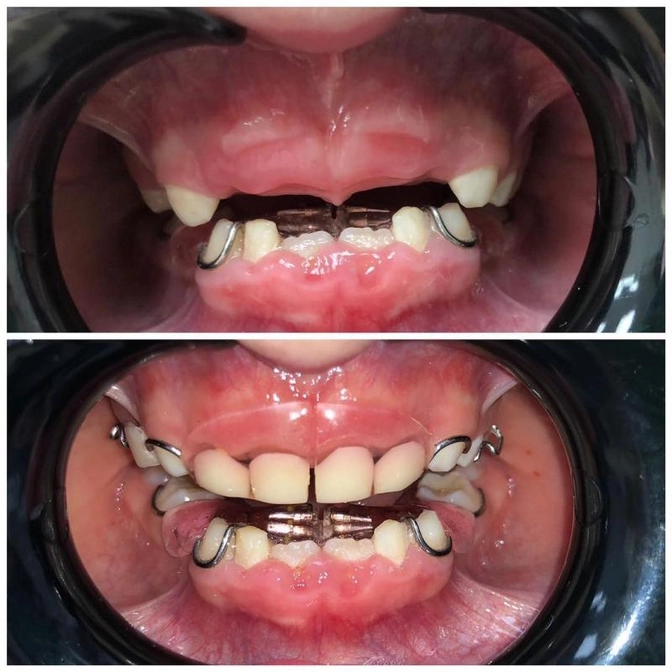

Итак, девочке 4,5 года

Из явного: отсутствуют 4 центральных зуба.

Наш ортодонт назначила изготовление заместительной пластинки на верхнюю челюсть.

Вот так это выглядит.

Это индивидуально изготовленный аппарат с пластмассовыми зубами в составе.

Внешне напоминает протез, который носят бабушки-дедушки.

Только детская пластинка намного меньше.

Ещё обратите внимание на нижнюю челюсть.

Два центральных зуба уже поменялись на постоянные.

Смена довольно ранняя (напомню: ребёнку 4.5, а эти зубы начинают меняться в среднем в 6 лет)

Ещё: Смотрите, какие волнистые края у этих новых зубов.

Это абсолютная норма, такими прорезаются зубы у всех без исключения.

Потом эти края немного стираются и все становится ровненько.

На нижней челюсти тоже установлен пластиночный аппарат.

Цель его ношения - стимулирование роста челюсти, чтобы зубам было не тесно.